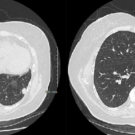

A 74-year-old man with a history of oxygen-dependent chronic obstructive pulmonary disease, hypertension, tobacco use disorder, recurrent left pleural effusion, and latent tuberculosis was admitted at an...